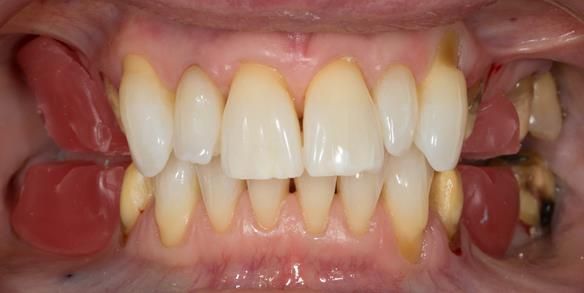

This newsletter describes in step by step detail Angela's transition through immediate partial dentures to crown supported definitive metal based dentures.

This 58 year old woman was referred to me by her general dental practitoner for treatment.

The clinical situation and treatment process is shown in detail below with photographs. I (Finlay Sutton) provided the clinical work and Rowan Garstang provided the technical work.